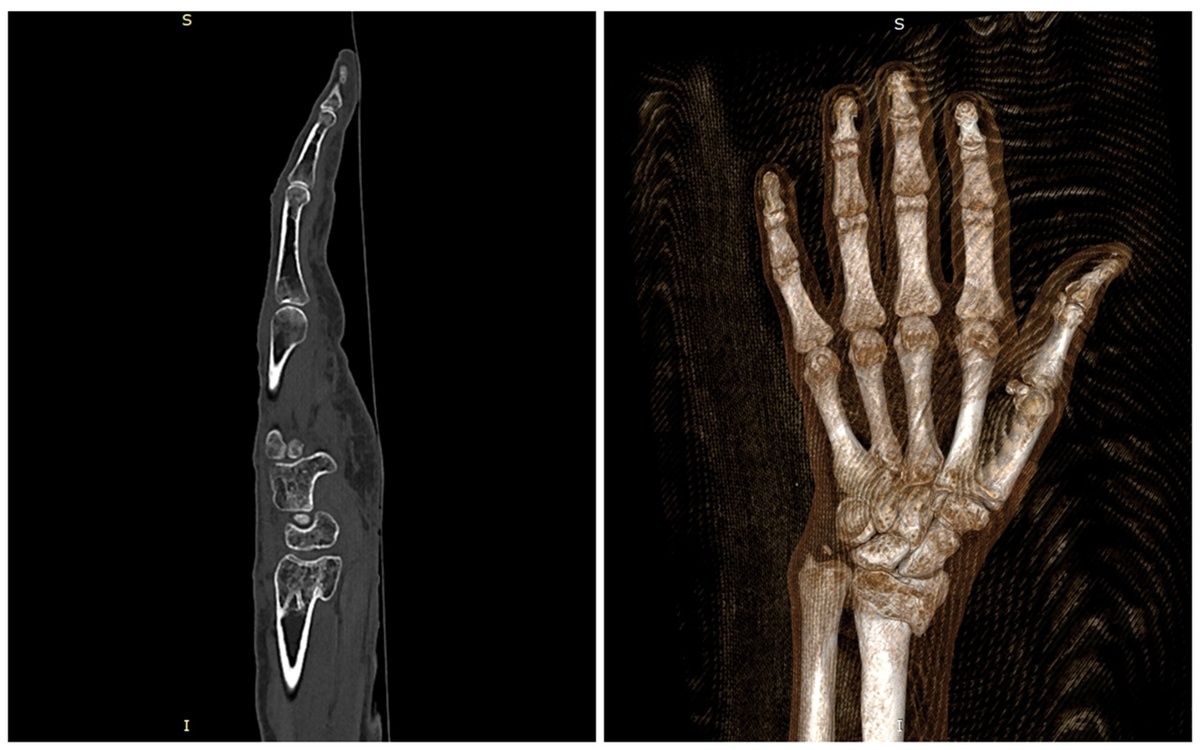

Ещё в ноябре 2024 года 76-летняя преподаватель поскользнулась во время гололёда и получила перелом лучевой кости правой руки. Спустя время рука восстановилась, перелом зарос, но пациентка обратила внимание на деформацию в области травмы. За помощью она обратилась в ННИИТО им. Я.Л. Цивьяна. Об этом рассказала пресс-служба медицинского учреждения.

Отличия травмированной руки от здоровой были заметны невооружённым глазом. К тому же запястье постоянно отекало и сильно болело, возникли ограничения в движении и слабость кисти. Врачами был предложен один единственный выход, как можно исправить ситуацию — хирургическое вмешательство.

«В операционной мы выполнили реконструктивное хирургическое вмешательство. Сделали корригирующую остеотомию дистального метаэпифиза правой лучевой кости, вернули смещенный фрагмент в правильное положение, заполнили образовавшийся костный дефект аллокостью — а в завершение зафиксировали кость титановой пластиной. Таким образом мы восстановили правильную анатомию повреждённого предплечья и взаимоотношения костей в лучезапястном суставе», — поделилась хирург травматолого-ортопедического отделения № 1 ННИИТО Виктория Клименкова.

Женщину уже через 2 дня после операции отпустили домой. При правильном восстановлении и соблюдении рекомендаций в будущем пациентку боль и ограничения больше не побеспокоят.